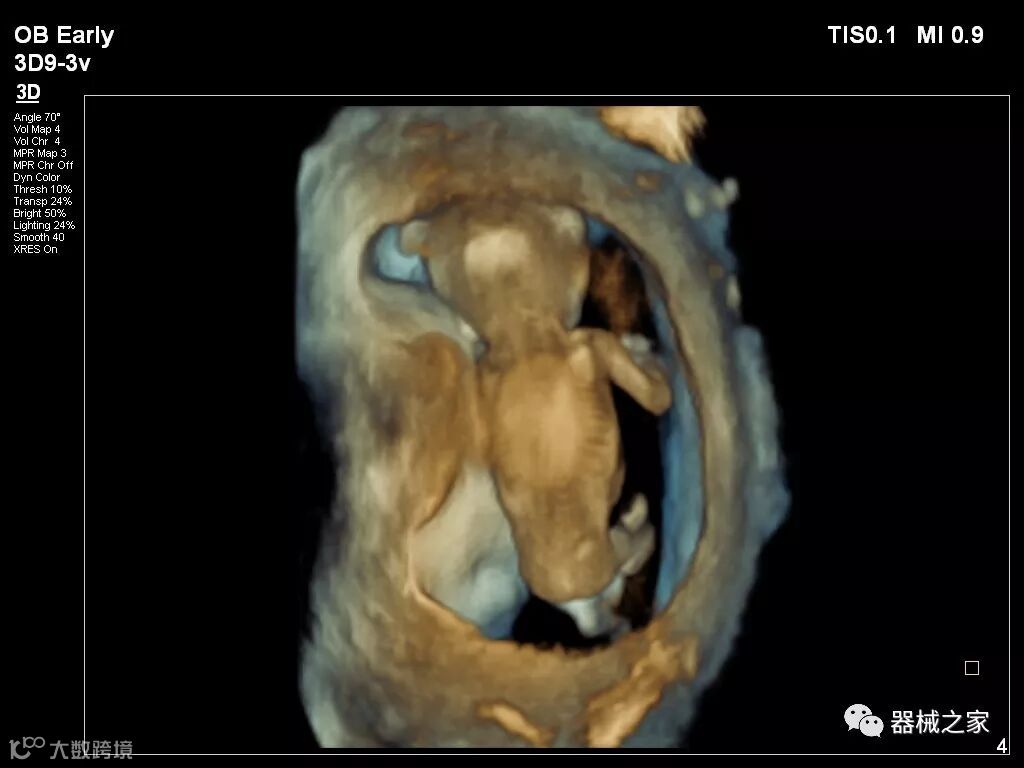

在RSNA 2018上发布的新成像被开发用于解决胎儿心脏和脑部成像问题。由于体积小且心率极快,因此难以进行详细的胎儿心脏评估。在18周时,胎儿的心脏大小与橄榄相当,每分钟跳动约150次。此外,结构本身非常复杂,婴儿不断运动,它始终是一个移动的目标。成像很重要,因为先天性心脏缺陷会影响全球每110个婴儿中的一个。

GE Healthcare用于胎儿超声的胎儿心脏和血管分析软件,在Voluson E10上提供,有助于在不到三分钟的时间内评估胎儿的心脏形状,大小和收缩性。称为辐射流的功能以三维视图显示血流。它还可以帮助显示缓慢流动的血液,例如神经血管循环。

Voluson E10

2018年发布的另一个例子是飞利浦的TrueVue,它提供照片般逼真的渲染,并能够在三维超声图像上改变光源的位置。它允许用户改变照明条件以提高对比度。可以移动光源以改变阴影并增加更多深度感知。还可以推动光源穿过组织以对解剖结构进行背光。